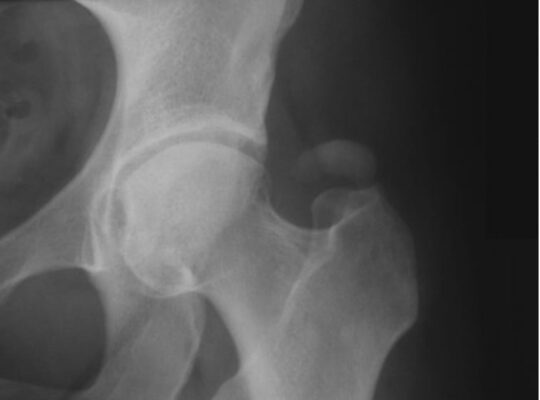

X quang khớp háng trong GTPS thường bình thường, và có thể loại trừ các chẩn đoán phân biệt thường gặp như thoái hoá khớp háng hoặc gãy xương. Đôi khi có thể thấy các nốt vôi hóa ở vùng túi thanh mạc hoặc trong chỗ bám của gân cơ (bệnh lý gân cơ canxi hoá).

X quang khớp háng một bệnh nhân bị viêm gân can xi hoá do lắng đọng tinh thể hydroxyapatie ở gân cơ mông phía trên mấu chuyển lớn